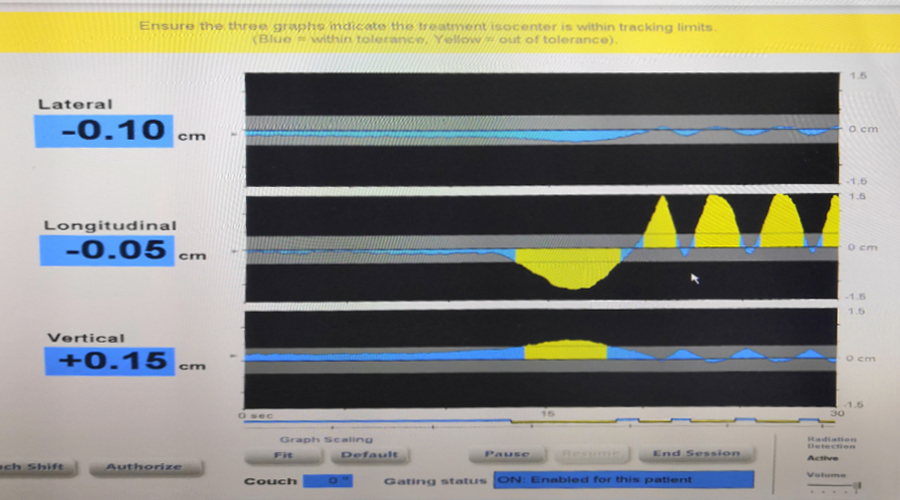

患者在治疗时进行呼气末屏气的 Calypso 实时肿瘤跟踪情况。

右边显示为患者自由呼吸时的肿瘤运动,中间为患者吸气呼气后再屏气,

左边显示患者屏气时肿瘤运动在阈值内,加速器正常出束。